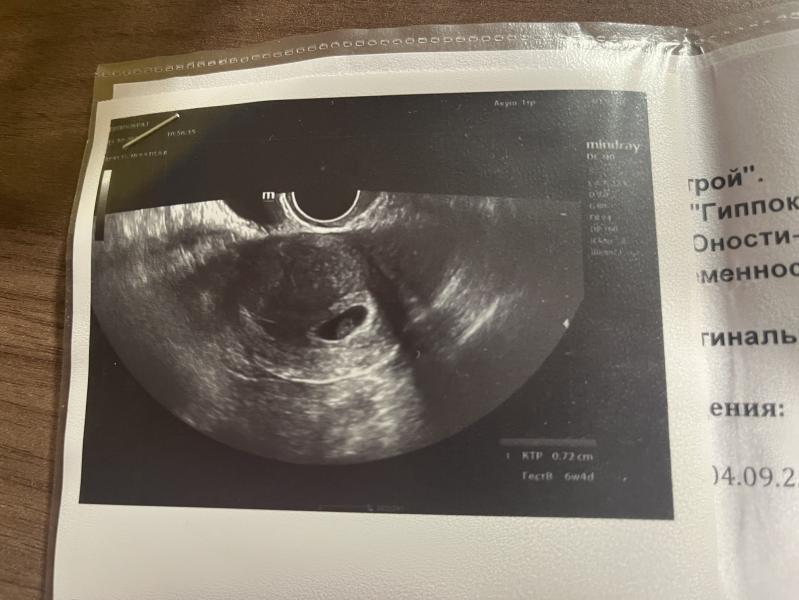

Когда вставать на учет после УЗИ с сердцебиением

Сходила вчера на узи. Сердце биение есть. Можно теперь вставать на учет 🤭